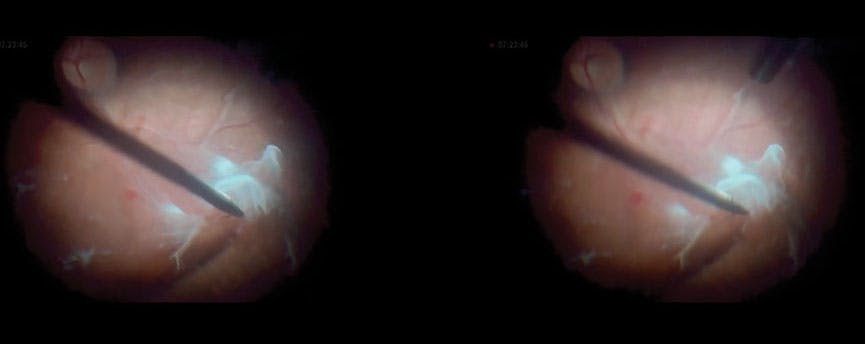

Tissue characteristics, such as resistance and thickness, make management of diabetic retinopathy cases increasingly reliant on the surgeon’s skill. Proper force application and consideration of vectors and directions are essential to accurately target specific tissues. In the context of diabetic retinopathy, fibrovascular tissue peeling must be conducted with utmost care and delicacy.

When managing a patient with severe diabetic retinopathy and retinal detachments (Video 3), I used 25-gauge serrated forceps, which provides excellent grip on both the ILM and some ERM, allowing the use of gentle and controlled movements. Rushing the procedure or applying excessive force can lead to tearing of the membrane, potentially causing hemorrhage and other complications.

This technique involves securing the fibrovascular tissue and employing horizontal movements, which allows the forceps to engage the membrane with minimal traction. Some ERMs may not be stained with brilliant blue G (the dye that was used in this procedure). As a result, when the ILM is peeled horizontally, it also removes the unstained ERM, achieving a double peel. By removing both membranes from the macular area, this technique effectively relieves traction.